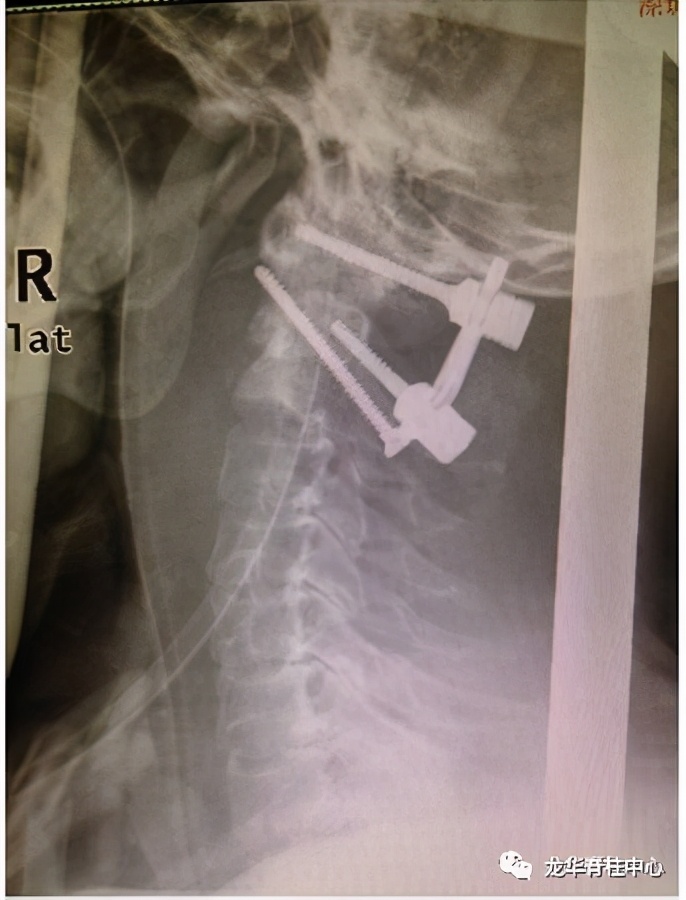

显微镜下寰枢椎脱位经口松解、后路固定术

开展深圳市首例寰枢椎脱位经口咽松解、后路椎弓根钉板内固定术